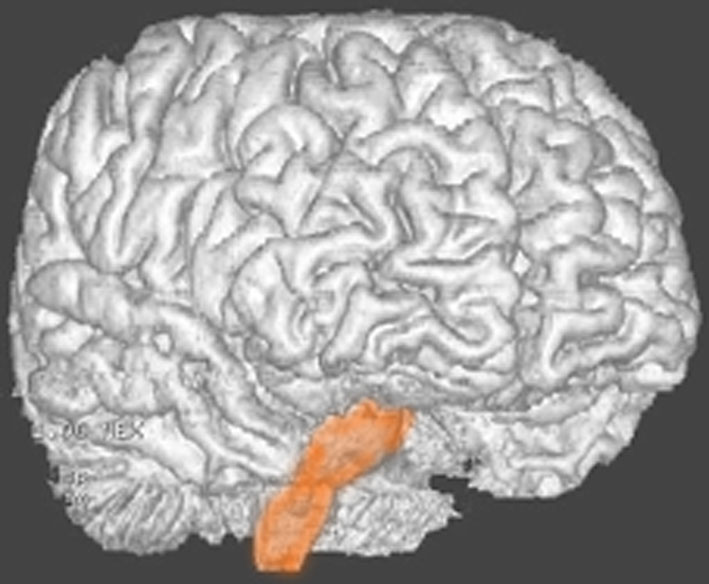

脳幹部の解剖図

- 脳の底面からしか見えないのでいろいろな角度から見ています

これは脳の中心部を縦切りにした写真です。脳幹部は上から順に,中脳 midbrain (黄色),橋 pons(オレンジ),延髄 medulla oblongata(ピンク)と呼ばれます。